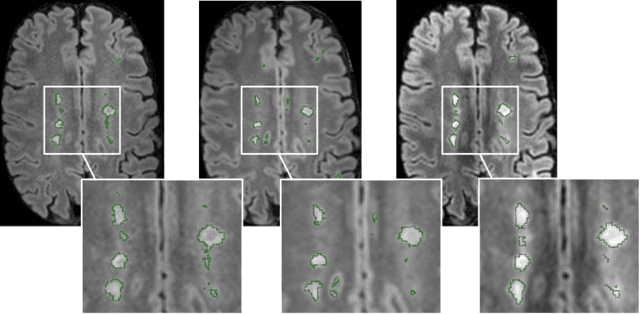

Abstract:The evaluation of white matter lesion progression is an important biomarker in the follow-up of MS patients and plays a crucial role when deciding the course of treatment. Current automated lesion segmentation algorithms are susceptible to variability in image characteristics related to MRI scanner or protocol differences. We propose a model that improves the consistency of MS lesion segmentations in inter-scanner studies. First, we train a CNN base model to approximate the performance of icobrain, an FDA-approved clinically available lesion segmentation software. A discriminator model is then trained to predict if two lesion segmentations are based on scans acquired using the same scanner type or not, achieving a 78% accuracy in this task. Finally, the base model and the discriminator are trained adversarially on multi-scanner longitudinal data to improve the inter-scanner consistency of the base model. The performance of the models is evaluated on an unseen dataset containing manual delineations. The inter-scanner variability is evaluated on test-retest data, where the adversarial network produces improved results over the base model and the FDA-approved solution.